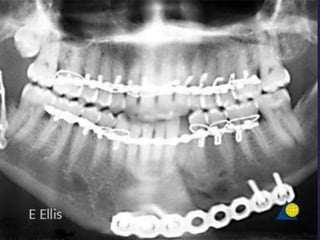

• #29 Panoramic x-ray 6 weeks after treatment of left angle fracture with single miniplate. The fracture is grossly mobile, infected, and the plate has become loose

• #30 The fracture was debrided, the plate removed, the infection drained, and the patient placed on antibiotics to control infection. Once infection has subsided, the patient was taken to surgery and the fracture exposed through a submandibular approach. The fibrous tissue between the fragments was debrided and the fragments decorticated.

• #31 The occlusion was reestablished with MMF. A reconstruction plate was then adapted and secured to provide load-bearing fixation across the fracture gap.. Particulate autogenous bone was placed into the fracture gap and the incision closed in layers.

• #32 Panoramic x-ray taken 10 months postoperatively showing bone filling fracture gap